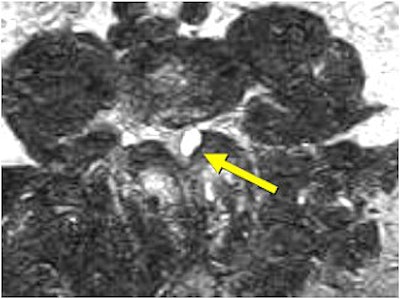

| Above and below, left facet synovial cyst at L4-L5 (1.5 cm superoinferiorly by 1.1 cm anteroposteriorly by 0.8 cm transversely) under axial loading. This synovial cyst caused pronounced compromise of the left lateral recess with severe left lateral recess stenosis, as well as compression and anterior displacement of the left L5 descending nerve root as it exits the thecal sac. The left lateral thecal sac is compressed severely and displaced nearly to the midline. |